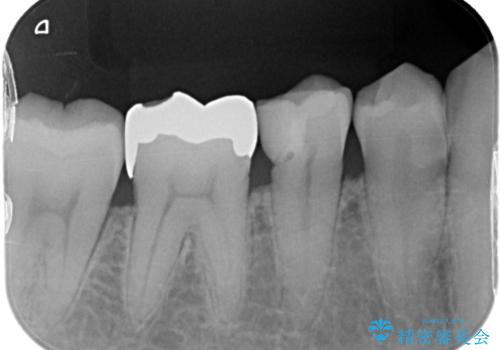

- 歯と歯の間によくものが詰まるということで来院された患者様です。

銀歯のある部分によくものが詰まるようで、診断の結果セラミックにて治療を行う計画を立てて

銀歯を外し他の歯も虫歯があったためそちらも一緒に治療を行いました。

銀歯だったところは、歯質を削る量が多かったためクラウンにて治療し、前後の歯に関してはインレーにて治療を行なっております。